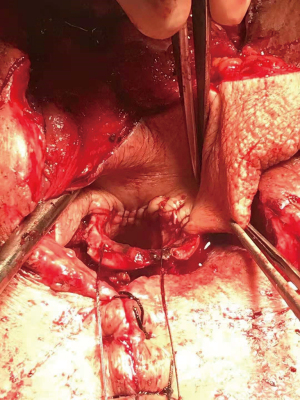

One month later, the patient was readmitted for preoperative evaluation. After neoadjuvant chemotherapy, CT revealed the location of the lesion showed a chemotherapy-induced change. Multiple air spaces were visible at the primary lesion site, and there was no obvious tumor regression (Figure 1). Esophagoscopy suggested chemotherapy-induced changes at 15 to 20 cm from the incisors, and a neoplasm with ulcers was still visible. A rupture was suspected at 20 cm from the incisors, with occasionally emerging bubbles, suggesting a possible esophageal fistula (Figure 2). Tracheoscopy revealed that the mucosa of the tracheal membrane about 5 cm above the tracheal carina was significantly swollen, and the nearby lumen was narrow (Figure 3).